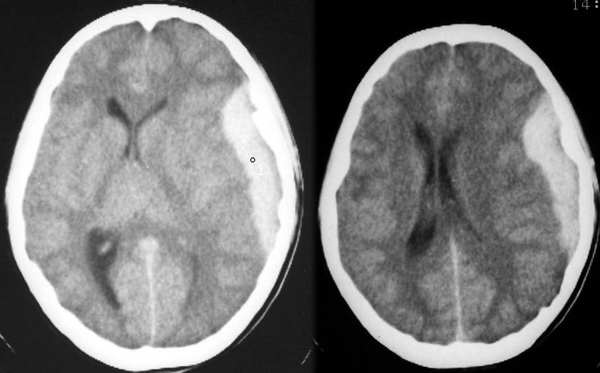

患者女,13岁,头痛头昏数天,一月前有外伤史

从影像上看:应该是硬膜下血肿吧,外形成d字形,跨越了颅缝,内边界不太清,中线向右移位。分期就不太好分了,外伤时间比较长,密度还是比较均匀的。应询问病史,特别是外伤后的情况。

根据病史首先考虑亚急性硬膜下血肿:占位效应明显,局部脑组织受压向内移位,左侧脑室受压变窄;但受伤一个月,即使是迟发血肿,密度也不会达到56hu,内密度均匀,界线还较清晰,需增强区分脑膜瘤。

楼主反复提示:

1,颅内少见病例

患者女,13岁,头痛头昏数天,一月前有外伤史。

2,[注意]补充片子,ct值约56hu左右,请大家仔细分析,并不简单的骨窗没打,没有骨折,不是血肿,请大家猜猜,过两天公布病理结果。

一月前有外伤史,目前左侧颅骨内板下病灶密度很高而且均匀,用亚急性或慢性硬膜下血肿解释不了这么高的密度,占位明显,具体什么问题,思考中。

建议大家从别的角度考虑。

病理结果:原发淋巴瘤

原发淋巴瘤ct、mri无特征性,起源无定论。占颅内肿瘤的1%,好发基底节、丘脑、胼胝体,出血钙化少见,可以囊变变。mri :t1低信号,t2高信号,有明显强化,信号多变。

关于原发性颅内淋巴瘤的起源尚有争议,主要因为颅内无淋巴结构。目前较公认的是病变起源于血管周围间隙的多能干细胞或单核吞噬细胞系统,因此淋巴瘤发病部位具有一定的特征性,即主要发生于轴内,靠近脑表面或中线区,此区的血管周围间隙比较明显。

影像表现:原发性颅内淋巴瘤的影像学表现具有特征性,病变可单发,亦可多发,分布广泛,75%邻近脑室系统或脑膜。ct平扫典型的表现为等或稍高密度,周围水肿较轻微;mr显示病变为等t1信号影,t2表现各异,主要与病变本身结构有关,常见的表现为等或低t2信号影。淋巴瘤周围水肿较轻微,占位效应低于恶性胶质瘤、转移瘤。增强检查病变呈明显均匀强化,主要表现为团块状、握拳样强化。环形强化少见,只见于出现坏死、囊变的病人。淋巴瘤可以沿软脑膜或室管膜播散。

以下影像学表现应首先考虑原发性颅内淋巴瘤:ct平扫呈等或高密度;mr呈等t1、等t2信号影,增强检查呈握拳样或团块状强化;肿瘤的占位效应轻微与肿瘤的大小不成比例;位于脑表面或近中线部位(血管入脑的部位);非免疫功能低下的病人患有淋巴瘤时,肿瘤内坏死、囊变少见。

鉴别诊断: 1.淋巴瘤靠近中线时,多贴近室管膜或胼胝体,又同时伴有坏死、囊变时,需与恶性胶质瘤鉴别,后者病变内囊变、坏死较多,周围水肿明显,占位效应较重,增强检查呈不均匀环形强化,临床症状较凶险。2.多发淋巴瘤需与转移瘤鉴别,前者主要位于大脑半球深部。发生于皮层的病变主要位于大脑前、中、后动脉的皮层支入脑后的近端最为常见,而转移瘤则位于皮髓质交界区,此时应仔细询问病史。3.淋巴瘤靠近脑表面时需与脑膜瘤鉴别,两者均表现为等t1、等t2信号影,但后者强化明显,可伴有脑膜尾征及邻近骨质的改变。